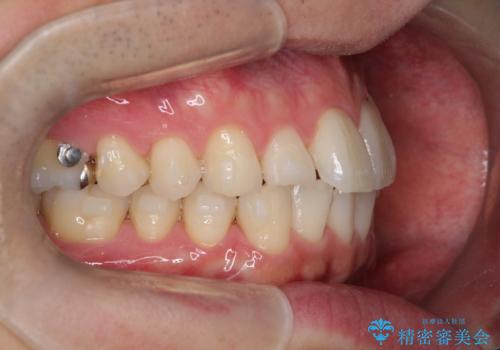

- 前歯の凸凹と顎の偏位を主訴に来院されました。

下顎の偏位を認めましたが、外科矯正を希望されなかったためできる範囲で顎の偏位を治すことができるよう治療を行なっております。

治療開始前に、下顎位の評価をおこなうことで、完成度の高い治療を行うことができました。